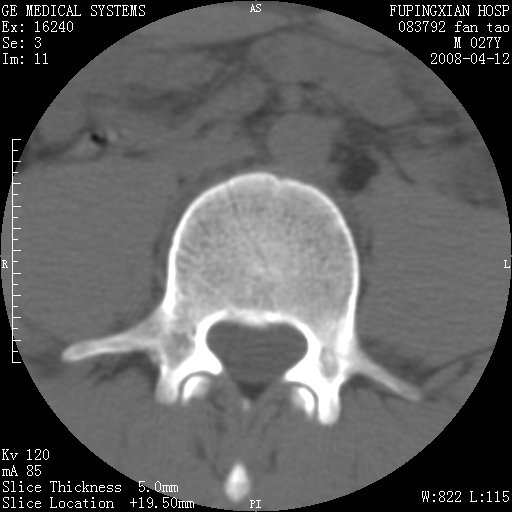

以下是引用前行在2008-4-13 13:53:00的发言:[br]椎间盘髓核终板下突出形成许莫氏结节及椎间盘突出,建议mr检查

以下是引用xclzq_910在2008-4-13 12:43:00的发言:[br]这个应该没什么了,椎间盘突出后反应性骨质吸收硬化.建议mr